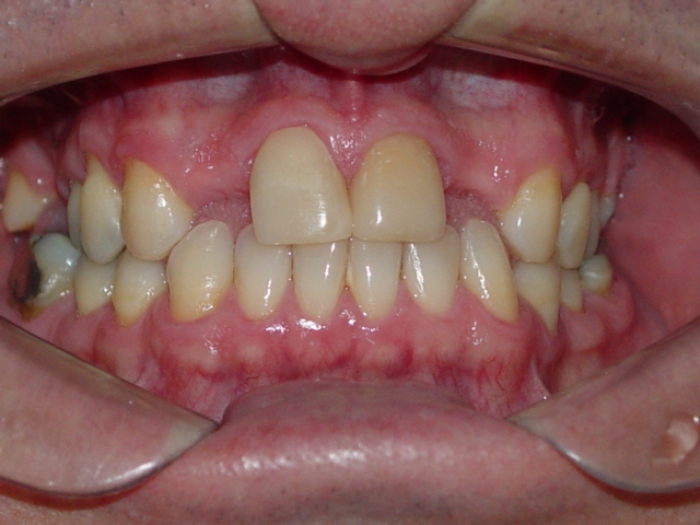

Próteses em porcelana

Sorriso final, do caso terminado em julho de 2012